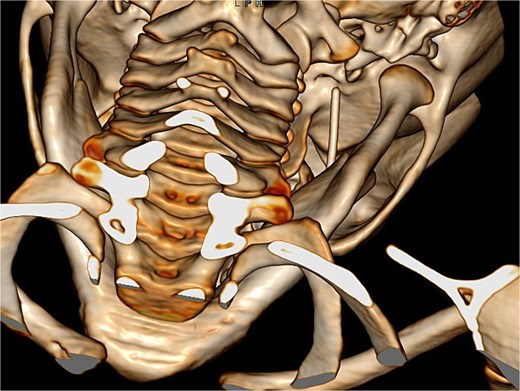

Neuronavigation-assisted surgery was then performed. The patient underwent a right pterional craniotomy (Fig. 3). Extradural dissection was conducted until Meckel’s cavum. The dura was carefully opened directly over the needle, which was completely removed through the craniotomy to avoid injury to the temporal lobe. The patient was admitted for a week of post-operative monitoring and received standard prophylactic intravenous medication. After 8 days, she had recovered well and was discharged. The patient remained asymptomatic throughout the entire process.

Pterional approach to reach the needle guided by neuronavigation.